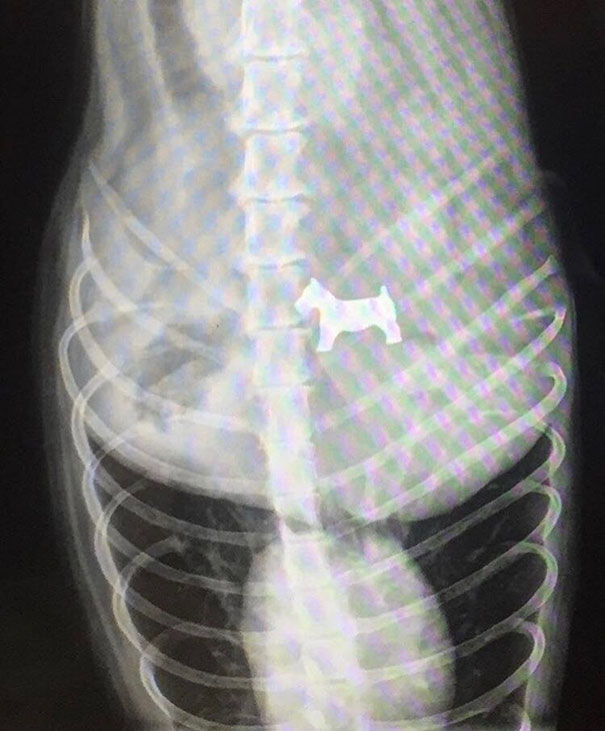

Questo cane è stato portato dal veterinario. Dalla risonanza risulta che abbia mangiato un cane del Monopoly.